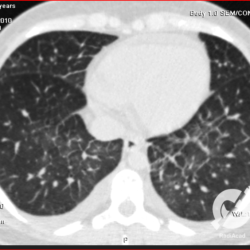

Consolidações alveolares e opacidades em vidro fosco peri-hilares, com espessamento septal e derrame pleural bilateral. Edema agudo de pulmão.